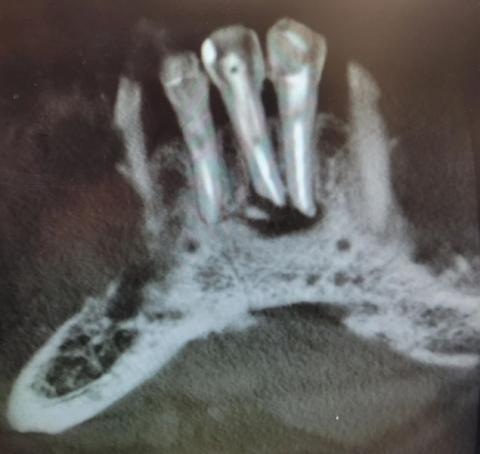

Severe Bone Infection Around Tooth Roots X-Ray Case

Severe Bone Infection Around Tooth Roots X-Ray Case Analysis

What Is Seen in This Case

The X-ray image shows severe bone loss and dark radiolucent areas around the roots of multiple teeth. The surrounding jawbone appears irregular, hollowed, and damaged, which strongly indicates advanced infection spreading through the bone.

The tooth roots are clearly visible with loss of normal bone support, a serious sign that the infection is no longer limited to the gums.

Most Likely Diagnosis

Based on X-ray findings, the most likely conditions include:

Advanced dental abscess

Chronic periapical infection

Jawbone infection (osteomyelitis)

Severe periodontal disease with bone loss

Failed or untreated root canal infection

This is an advanced-stage dental infection.